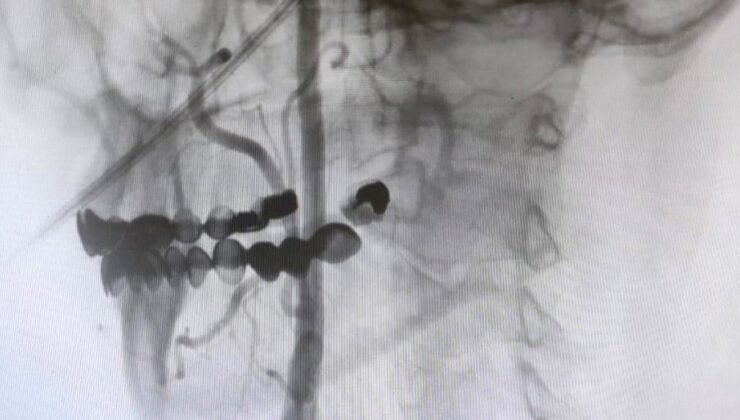

Manisa Şehir Hastanesi’nde girişimsel nöroloji ve girişimsel kardiyoloji uzmanlarının iş birliğiyle, beyni besleyen en büyük damarlar olan karotis (şah) damarlarındaki tıkanıklıklara karşı modern tedavi yöntemleri başarıyla uygulanıyor. Uzmanlar, bu damarlarda gelişen ciddi darlıkların inme (felç) riskini önemli ölçüde artırdığını belirtiyor. Bu nedenle, felç riskini azaltmak amacıyla hastalara stentleme işlemi uygulanıyor.

Girişimsel Nöroloji Uzmanı Doç. Dr. Ezgi Sezer Eryıldız, “Beynimizi besleyen en büyük damarlar karotis damarları yani şah damarlarıdır. Eğer bu damarlarda ciddi bir darlık olursa inme yani felç geçirme riski belirgin şekilde artmaktadır ve bu riski azaltmak için stentleme işlemi uygulanmaktadır. Rutin olarak hastalarımız bu açıdan değerlendiriliyor ve bu işlemi uyguluyoruz” dedi.

Şah damarındaki daralmaları açmanın iki yöntemi olduğunu ifade eden Girişimsel Kardiyoloji Uzmanı Doç. Dr. Ramazan Gündüz ise şunları söyledi:

“Boyun damarlarını açma işlemi iki şekilde yapılabilir. Bir karotis endarterektomi dediğimiz ameliyatla bir diğer yöntem ise perkutan girişim dediğimiz stent yöntemiyle açılabilir. Biz kliniğimizde nöroloji ve kardiyoloji olarak bir konsey yapıyoruz. Damarı ciddi tıkalı olan ve buna bağlı felç geçirmiş hastalarda bu konseyde hastaya işlem yapıp yapmama kararı veriyoruz. Verdiğimiz karar çerçevesinde eğer hastaya işlem kararı vermişsek femoral arter dediğimiz kasık arterinden bir şitle 6 ya da 7 F çapında bir şitle ince bir boruyla bu damara giriş yapıyoruz ve boyun damarlarına ulaşıyoruz. Özellikle teller, filtreler ve stentlerle bu damarları açıp hastanın tedavisini gerçekleştiriyoruz. İşlem ameliyatsız olduğu için hastamız ertesi gün rahat bir şekilde problem olmazsa işlemde taburcu olabiliyor bu işlemden sonra. Bu işlemin yapılması için özellikle anjiografinin olduğu girişimsel nöroloji uzmanının ve girişimsel kardiyoloji uzmanının olduğu ve bu konuda yeterli vaka tecrübesine ve deneyime sahip uzmanların olduğu merkezler gerekir. Bunu yapabilmek için belli bir vaka sayısına ulaşmak ve bu konuda tecrübeli olmak gerekiyor. Biz de Manisa Şehir Hastanesi’ndeki girişimsel kardiyoloji ve nöroloji uzmanları olarak bu işlemi kliniğimizde efektif bir şekilde gerçekleştiriyoruz.”